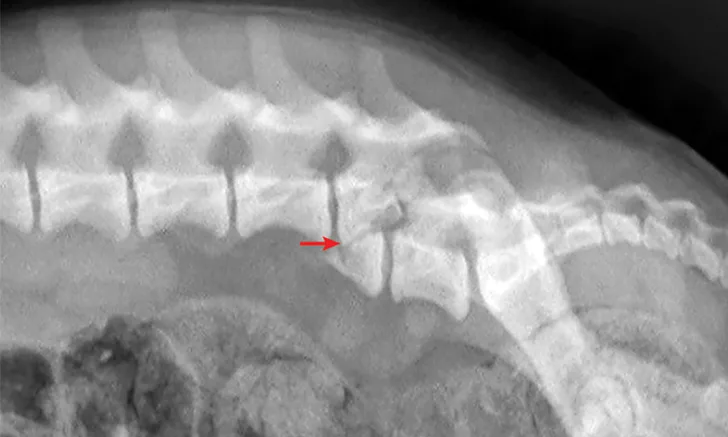

Surgical decompression and stabilization are often recommended for thoracic and lumbar injuries based on the degree of instability and risk for further vertebral column shifting and spinal cord damage. Surgical options include use of positive profile pins or screws with polymethylmethacrylate bone cement, external fixators, and vertebral body plates (Figure 5). Referral to a board-certified neurologist and/or surgeon is recommended for cases in which surgical therapy may be an option. Cats with sacrocaudal luxations may benefit from tail amputation, which removes a source of pain and prevents further traction damage to the sacral nerve roots.

Figure 5

Lateral radiographs taken pre- and postoperatively of a dog after being found in a ditch and presumably hit by a car. (A) There is a T8-T9 subluxation and (inconsequential) T8 spinous process fracture. (B) The subluxation was reduced and stabilized using fully threaded pins, Kirschner wire, and bone cement. The Kirschner wire encircles the pins and is intended to increase the strength of the bone cement. Ideally, these pins would have been placed with more craniocaudal angulation and the construct would have included a third implant spanning the luxation laterally to provide additional support.